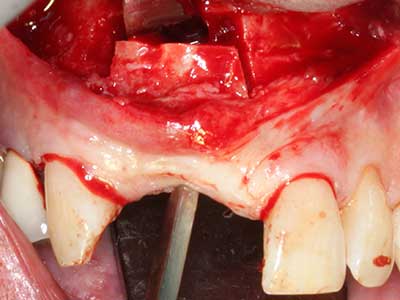

Fig. 2: difetto mascellare laterale, verticale e orizzontale, con linea del sorriso alta; indicazione per ricostruzione pre-impianto.

Fig. 3: la separazione basale del blocco è più semplice con i raccordi appositamente angolati.